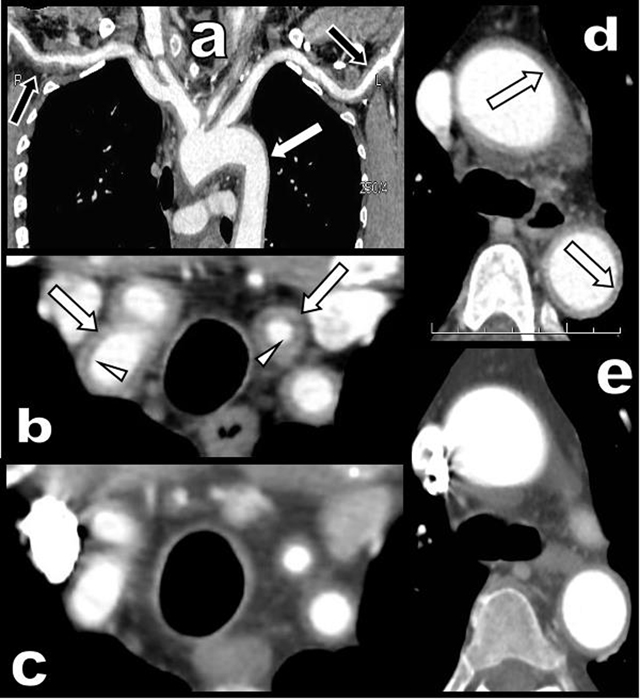

Figure 2

CT angiography of the aortic arch and of its large emerging arteries before (a, b, d) and after treatment (c and e).